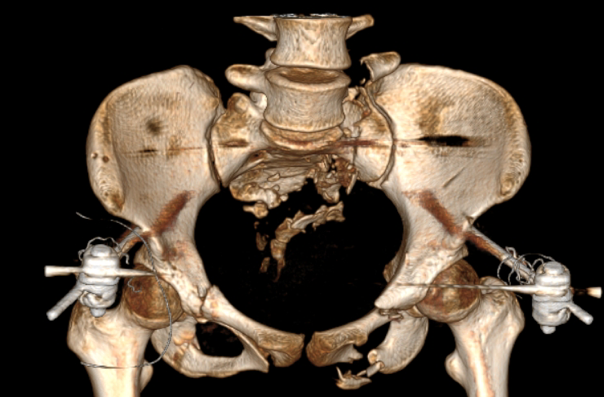

图五:术中透视验证复位结果

术中透视验证螺钉置入效果

经过2个半小时的“数智化微创手术”,患者手术切口仅有5个,切口平均长度小于1cm,术中出血量仅有50cc,“真·微创”治疗效果着实令人满意。智能化骨科手术机器人真正实现了看得见的‘快准稳’,不仅让医生有了‘超级助手’,真正意义上实现骨盆骨折微创治疗,同时对患者康复和术后生活质量极为有利。

图七:患者术后三天影像资料